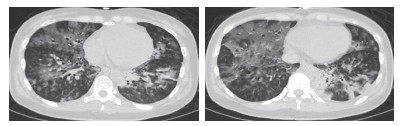

1 资料与方法 患者女性,29岁,以“恶心、呕吐1个月余,进食困难伴饮水呛咳半月,呼吸困难5 d,发热1 d”主诉收入北京世纪坛医院。患者病史长且复杂,笔者根据其先后就诊医院对其病史进行总结(表 1)。2018年5月10日患者在北京西客站候车过程中出现呼吸困难加重,随后出现呼之不应,立即送至本院急诊。至本院急诊抢救室时,患者生命体征心律166次/min,呼吸32次/min,血压80/47 mmHg(1 mmHg=0.133 kPa),氧饱和度80%,体温39.5℃,查体:浅昏迷,双瞳孔等大正圆,直径约2 mm,对光反射存在,无颈项强直,口周及口腔内可见较多清亮唾液,双肺呼吸音粗,双肺可闻及少量湿性啰音,左下肺为著,心律齐,各瓣膜听诊区未及杂音。腹部查体未见异常。双侧腱反射存在,双侧病理征阴性。血气:pH 6.95, PCO2 88 mmHg, PO2 48 mmHg, Lac 8.0 mmol/L, 故立即予气管插管、呼吸机辅助通气, 建立静脉通路补液及去甲肾上腺素泵入升压治疗,并立即收入本院急诊ICU。患者入院后主要血化验结果见表 2。心脏彩超提示弥漫性室壁运动异常,EF为45%,考虑感染相关心肌抑制。胸部CT提示双肺弥漫大小不等点片、斑片状高密度影,其内可见支气管走行,纵隔内可见多个大小不等淋巴结影,考虑双肺感染(图 1)。下肢血管超声、头颅CT、腹部CT均未见明显异常。患者入院后继续予气管插管接呼吸机辅助通气,呼吸机模式PC,起始参数:P 18 cmH2O(1 cmH2O=0.098 kPa),f 14次/min,PEEP 4 cmH2O,FiO2 40%;去甲肾上腺素静脉泵入及静脉补液升压治疗;肠内营养治疗;结合患者胸部CT及其他化验结果,诊断首先考虑重症肺炎,脓毒症,脓毒性休克,Ⅱ型呼吸衰竭,因此抗感染采用联合抗细菌、真菌及病毒全覆盖方案,同时予静脉输注人免疫球蛋白(IVIg)20 g/d ×5 d,静脉输注甲泼尼龙80 mg/12 h×4 d→40 mg/12 h×7 d→40 mg/d×3 d→甲泼尼龙片20 mg/d口服。经过上述治疗,患者体温逐渐下降至正常,神志逐渐转清,四肢肌力逐渐恢复至正常,呼吸机条件逐渐下调至模式PS,参数P 8 cmH2O,FiO2 40%,循环逐渐稳定并停用血管活性药物。复查主要血化验结果(表 3)均较前好转。抗感染治疗后前后2次复查胸部CT均提示肺炎较前吸收好转(图 2)。此时患者能脱机,但却不能拔管,且患者无咳嗽反射亦不能遵嘱吞咽。